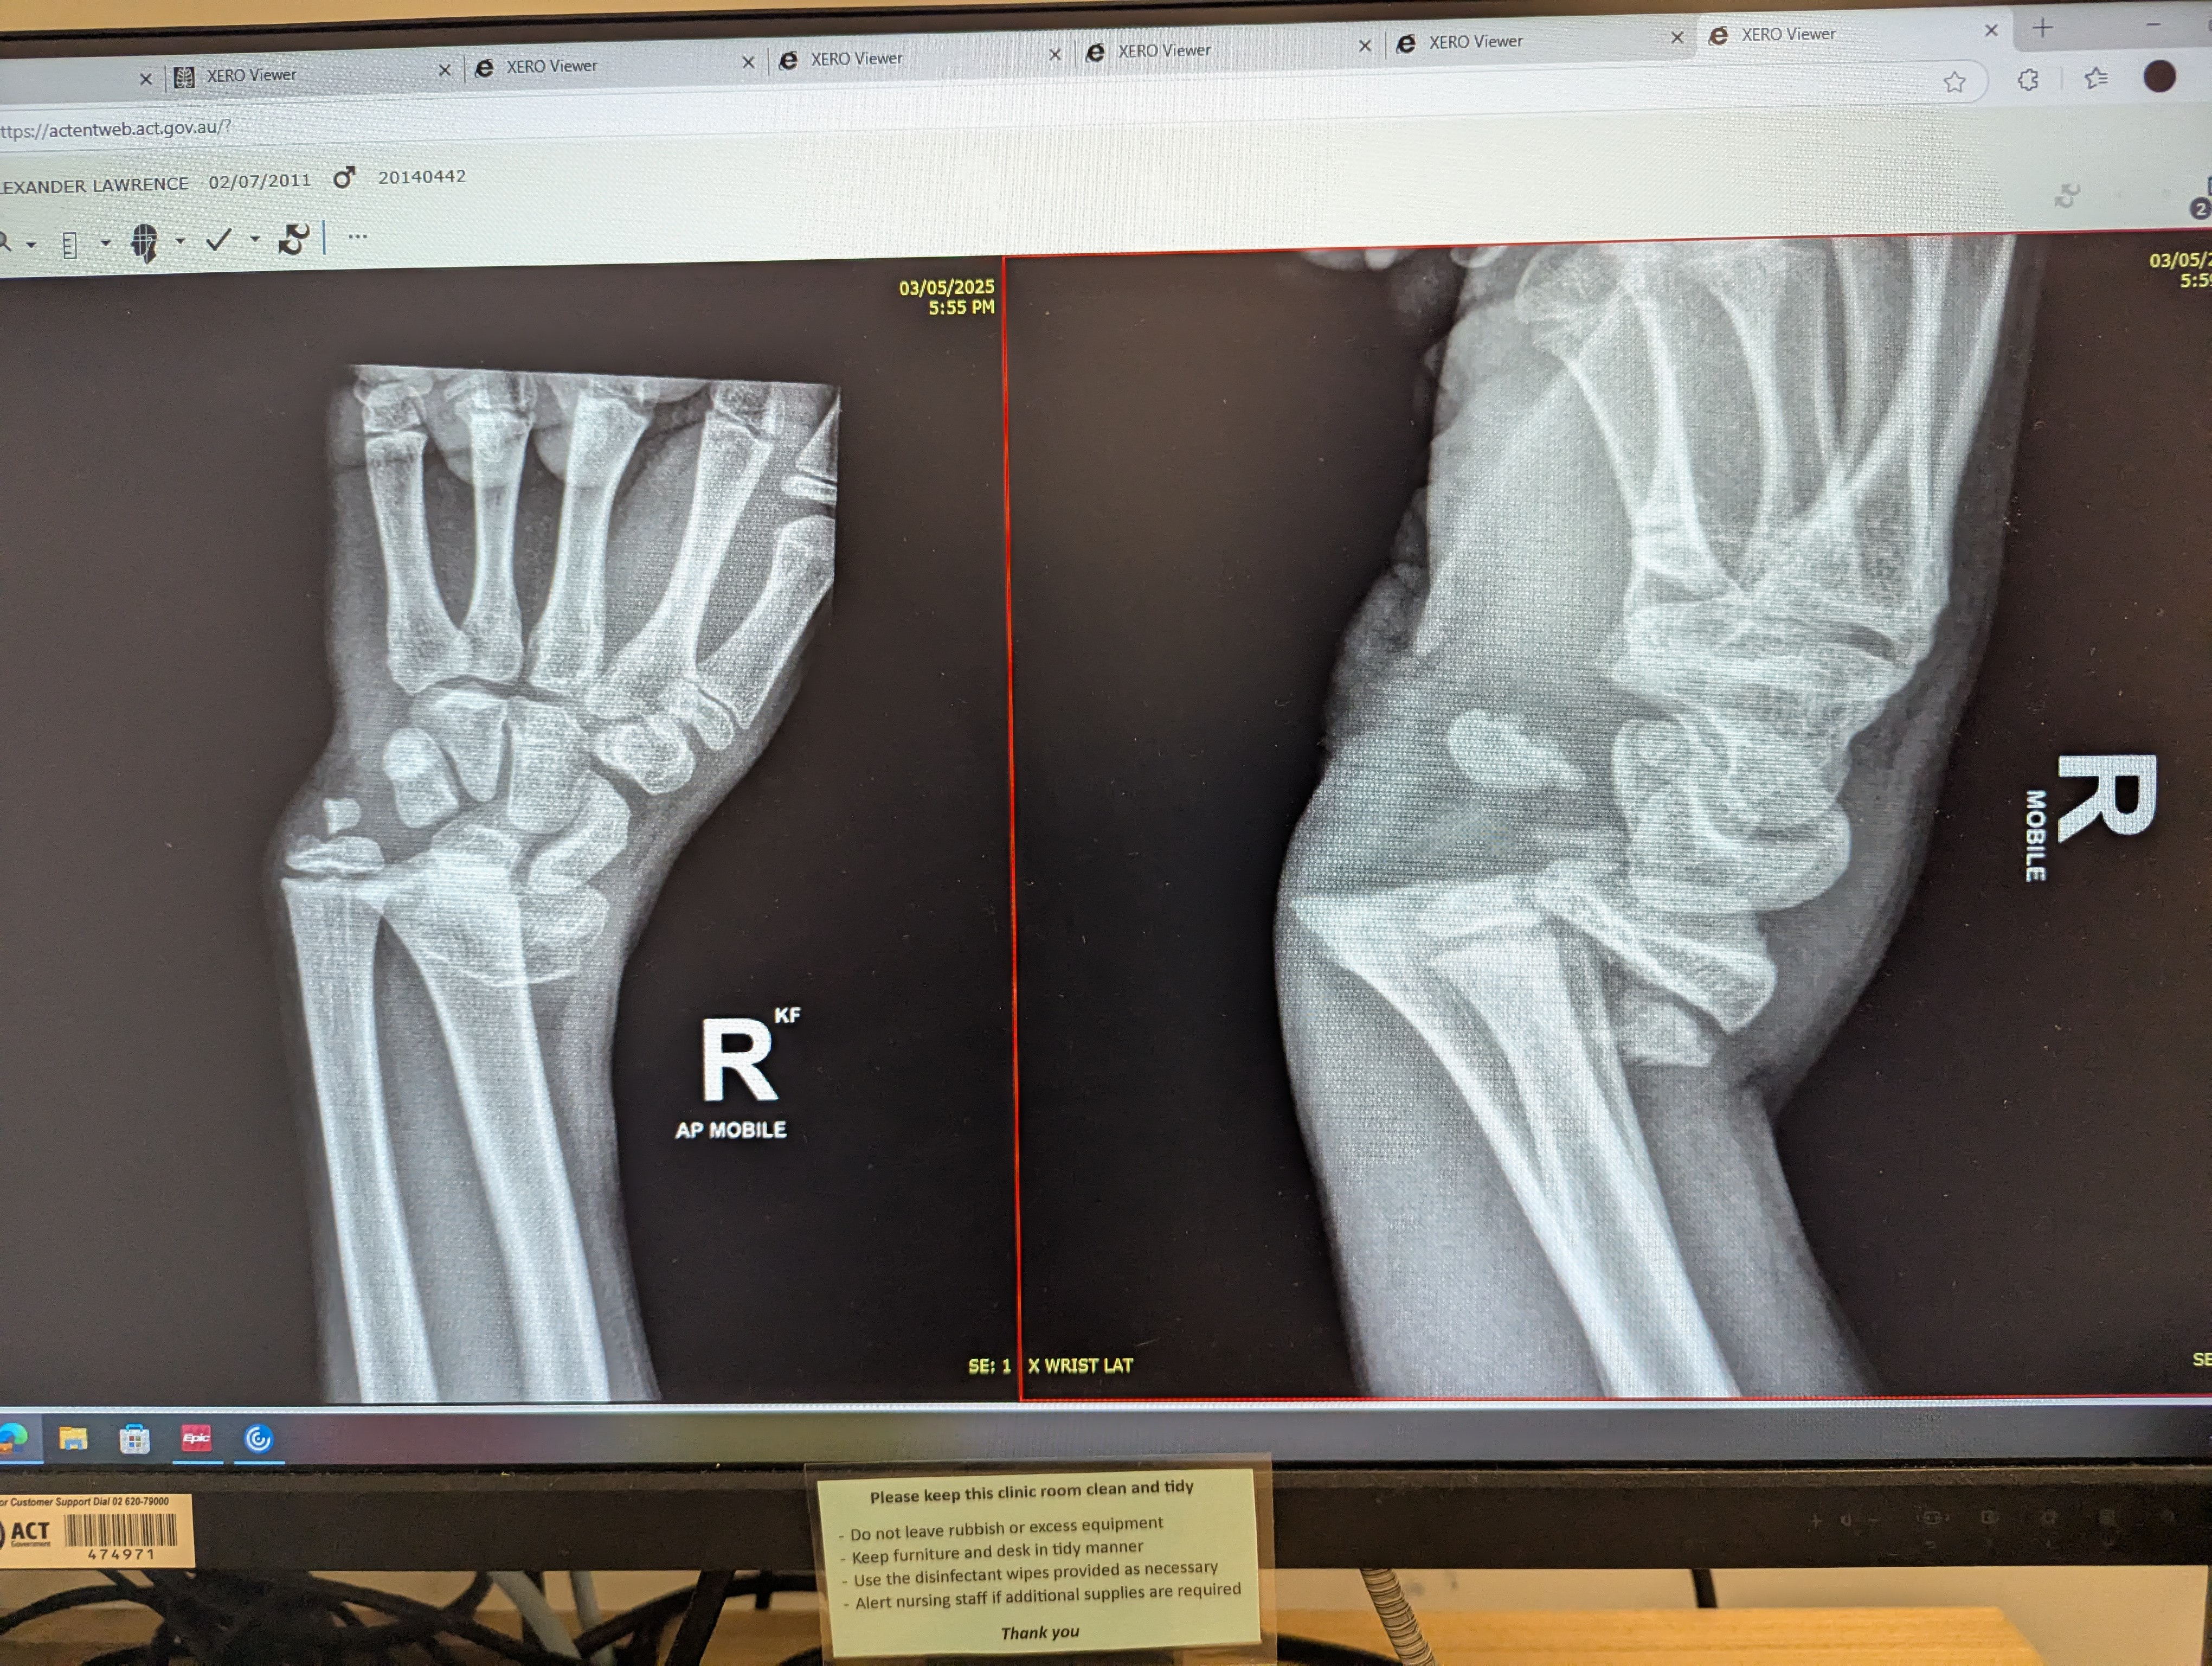

[deleted] the one on the right is the original injury, the one on the left is how the the first hospital I went to fixed it. it fine now but I lost all my muscle strength in my arm tho Gee, I'm glad I live in Australia, not The Democratic Republic Of Trump, or the hospital bills would have cost a fortune